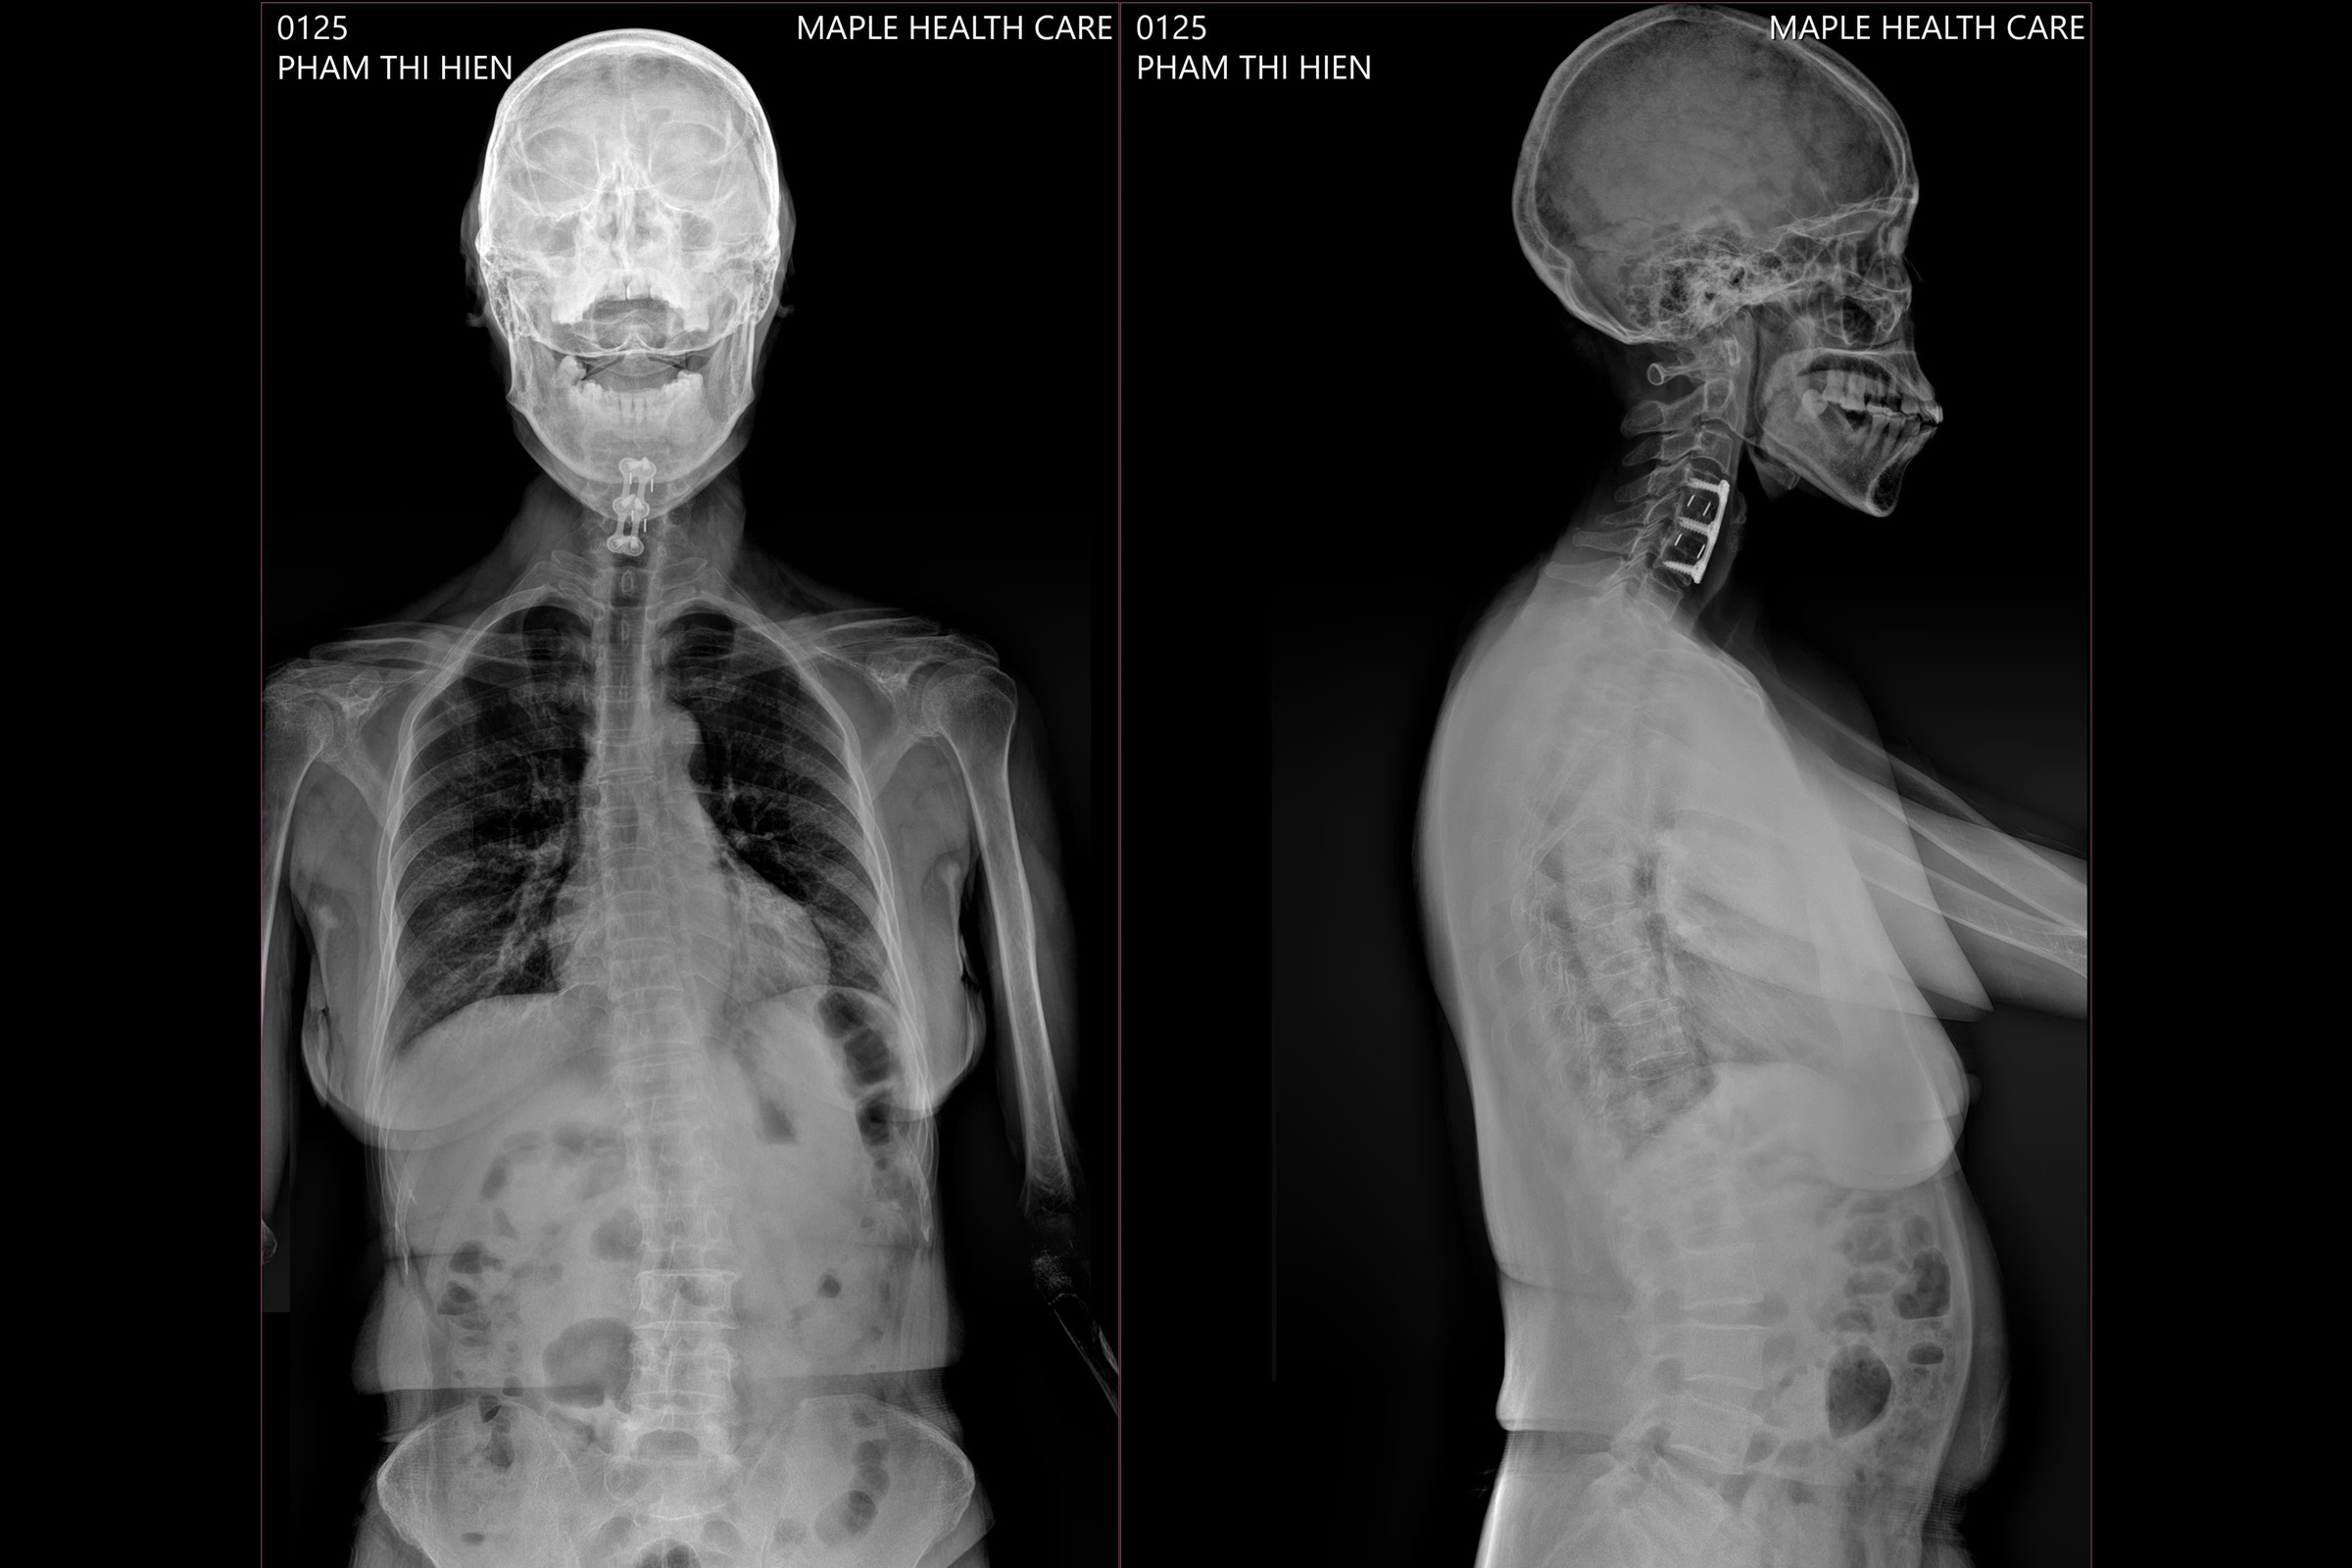

Dr. Paul cites the case of Hien, a 58-year-old patient from Gia Lai, who fractured two cervical vertebrae and damaged 5 spinal segments in an accident. After surgery to stabilize her spine, she experienced persistent lower back pain, limb weakness, and immobility. An examination at Maple Healthcare revealed misaligned vertebrae, directly impacting her mobility. Dr. Paul implemented a personalized treatment plan combining chiropractic adjustments, physiotherapy, and rehabilitation.

The examination revealed that Hien's cervical spine was misaligned, limiting her mobility. Photo: Maple Healthcare

Dr. Paul clarifies that chiropractic adjustments do not directly target the surgical area or the parts stabilized by screws and plates. Instead, they focus on adjusting adjacent vertebrae under compensatory pressure. This relieves nerve compression, reduces muscle stiffness, and restores spinal flexibility. When performed correctly, these adjustments can alleviate pain and muscle stiffness, improve mobility, enhance sleep quality, and support overall recovery.